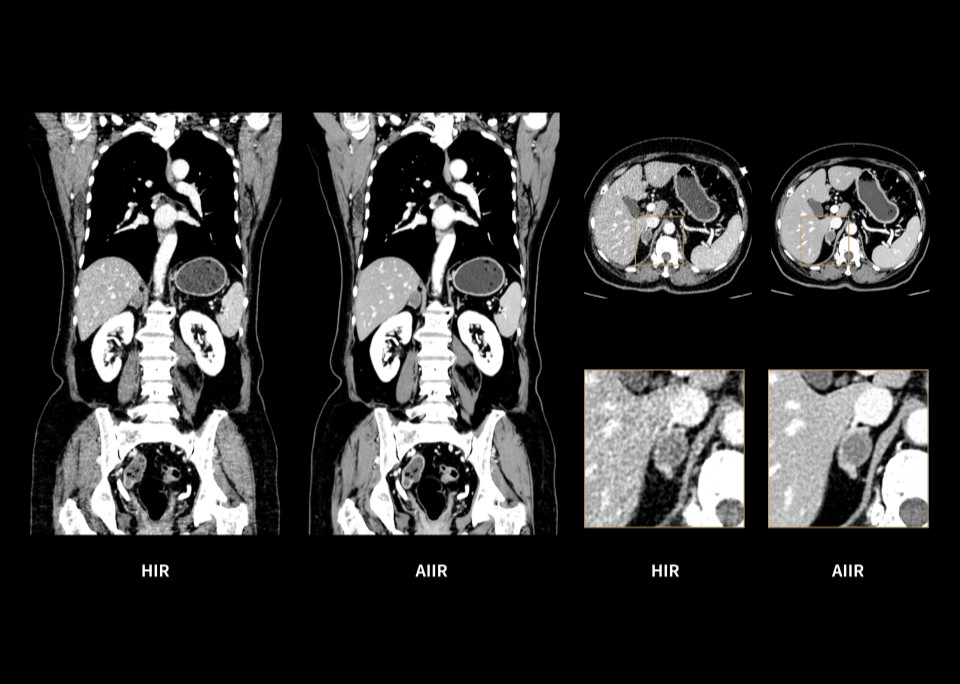

Throughout the iterative loop of forward and backward projection between the raw data domain and the image domain, AIIR consistently takes into account the accurate modeling of optics, noise, anatomy, and physics statistics. Additionally, AIIR integrates deep learning-based de-noising technology, supplanting the conventional regularization role of MBIR in the optimization reconstruction process.

In brief, AIIR utilizes deep learning-based AI technology to attain robust noise reduction and natural image texture, while incorporating MBIR technology to achieve precise anatomical structure representation and artifact suppression. This technique surpasses the limitations of using either MBIR or deep learning reconstruction (DLR) independently.